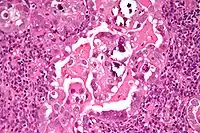

Histopathologically, uterine serous carcinomas is typically characterized by (1) nipple-shaped structures (papillae) with fibrovascular cores (2) marked nuclear atypia (irregularities in the nuclear membrane, enlarged nuclear size), (3) psammoma bodies and (4) cilia.